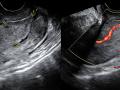

Tag: ultrassonografia transvaginal

Diagnóstico por imagem em ginecologia - Quinto ano medicina